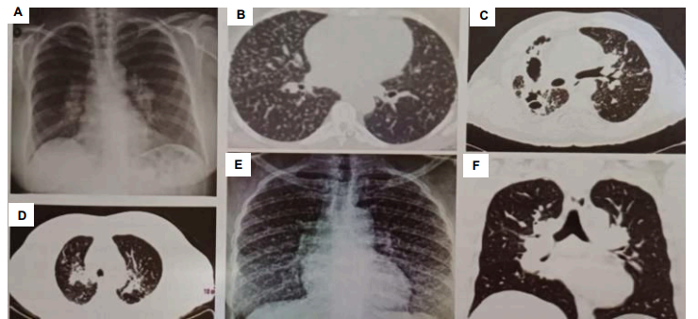

Analise as imagens a seguir:

Tendo em vista as imagens analisadas, é CORRETO afirmar que se trata, mais provavelmente, de qual patologia?